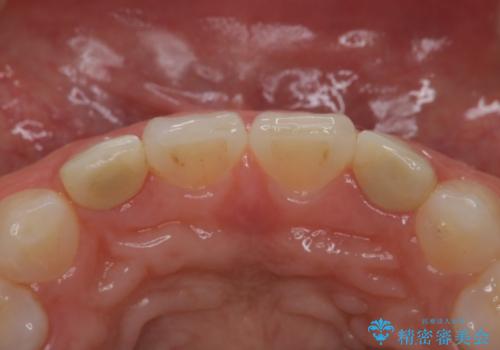

- 歯の形が気になるということで以前入っていたプラスチックのものから、セラミックでの治療を希望されたので行いました。

以前使用していた被せ物を除去して、仮歯に置き換えます。

その後、歯の最終的な形を作って型取りを行います。

当院で患者様の口腔内の写真を撮影し技工士さんに指示を出して完成します。